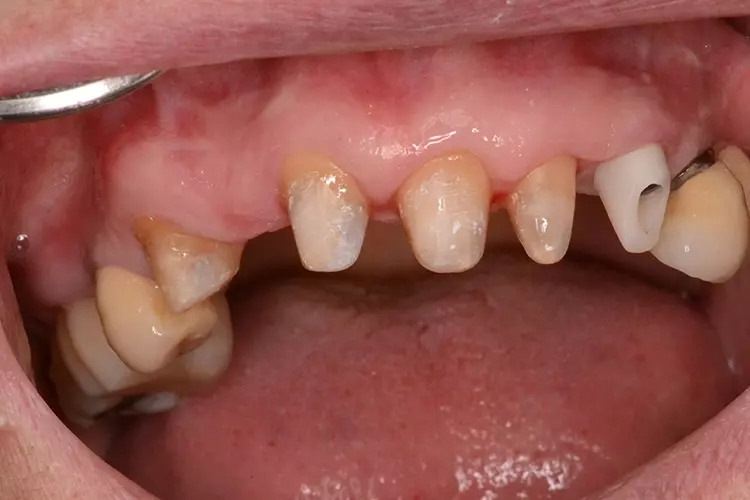

Neugestaltung der Front bei starken Zahnfehlstellungen

Bei dem heute 49-jährigen Patienten wurde seit Kindertagen versäumt, die Ober- und Unterkieferzahnbögen kieferorthopädisch auszurichten. Der Patient leidet seitdem stark unter seinen Zahnfehlstellungen.

Die Fraktur des stark elongierten Zahnes 21 war für den Patienten der Ausgangspunkt, sowohl die Front des Ober- als auch des Unterkiefers prothetisch überarbeiten zu lassen. Dabei wurde der frakturierte Zahn 21 durch ein navigiert eingesetztes Sofortimplantat ersetzt, während die verschachtelt stehenden Zähne 12 und 42 durch eine Brückenversorgung korrigiert wurden (Abb. 4a-j).